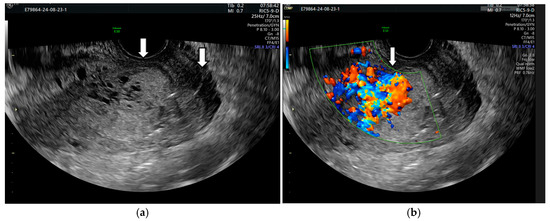

2. Case Presentation